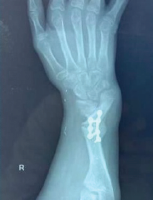

At 3 months, radiographs demonstrated complete good healing with cortical restoration (Fig. 5). The patient achieved a full range of motion without deformity. A structured rehabilitation program, including active and passive exercises and grip strengthening, ensured complete functional recovery.

Figure 5: Follow-up radiographs of the patient on anti-tubercular therapy for 3 months.